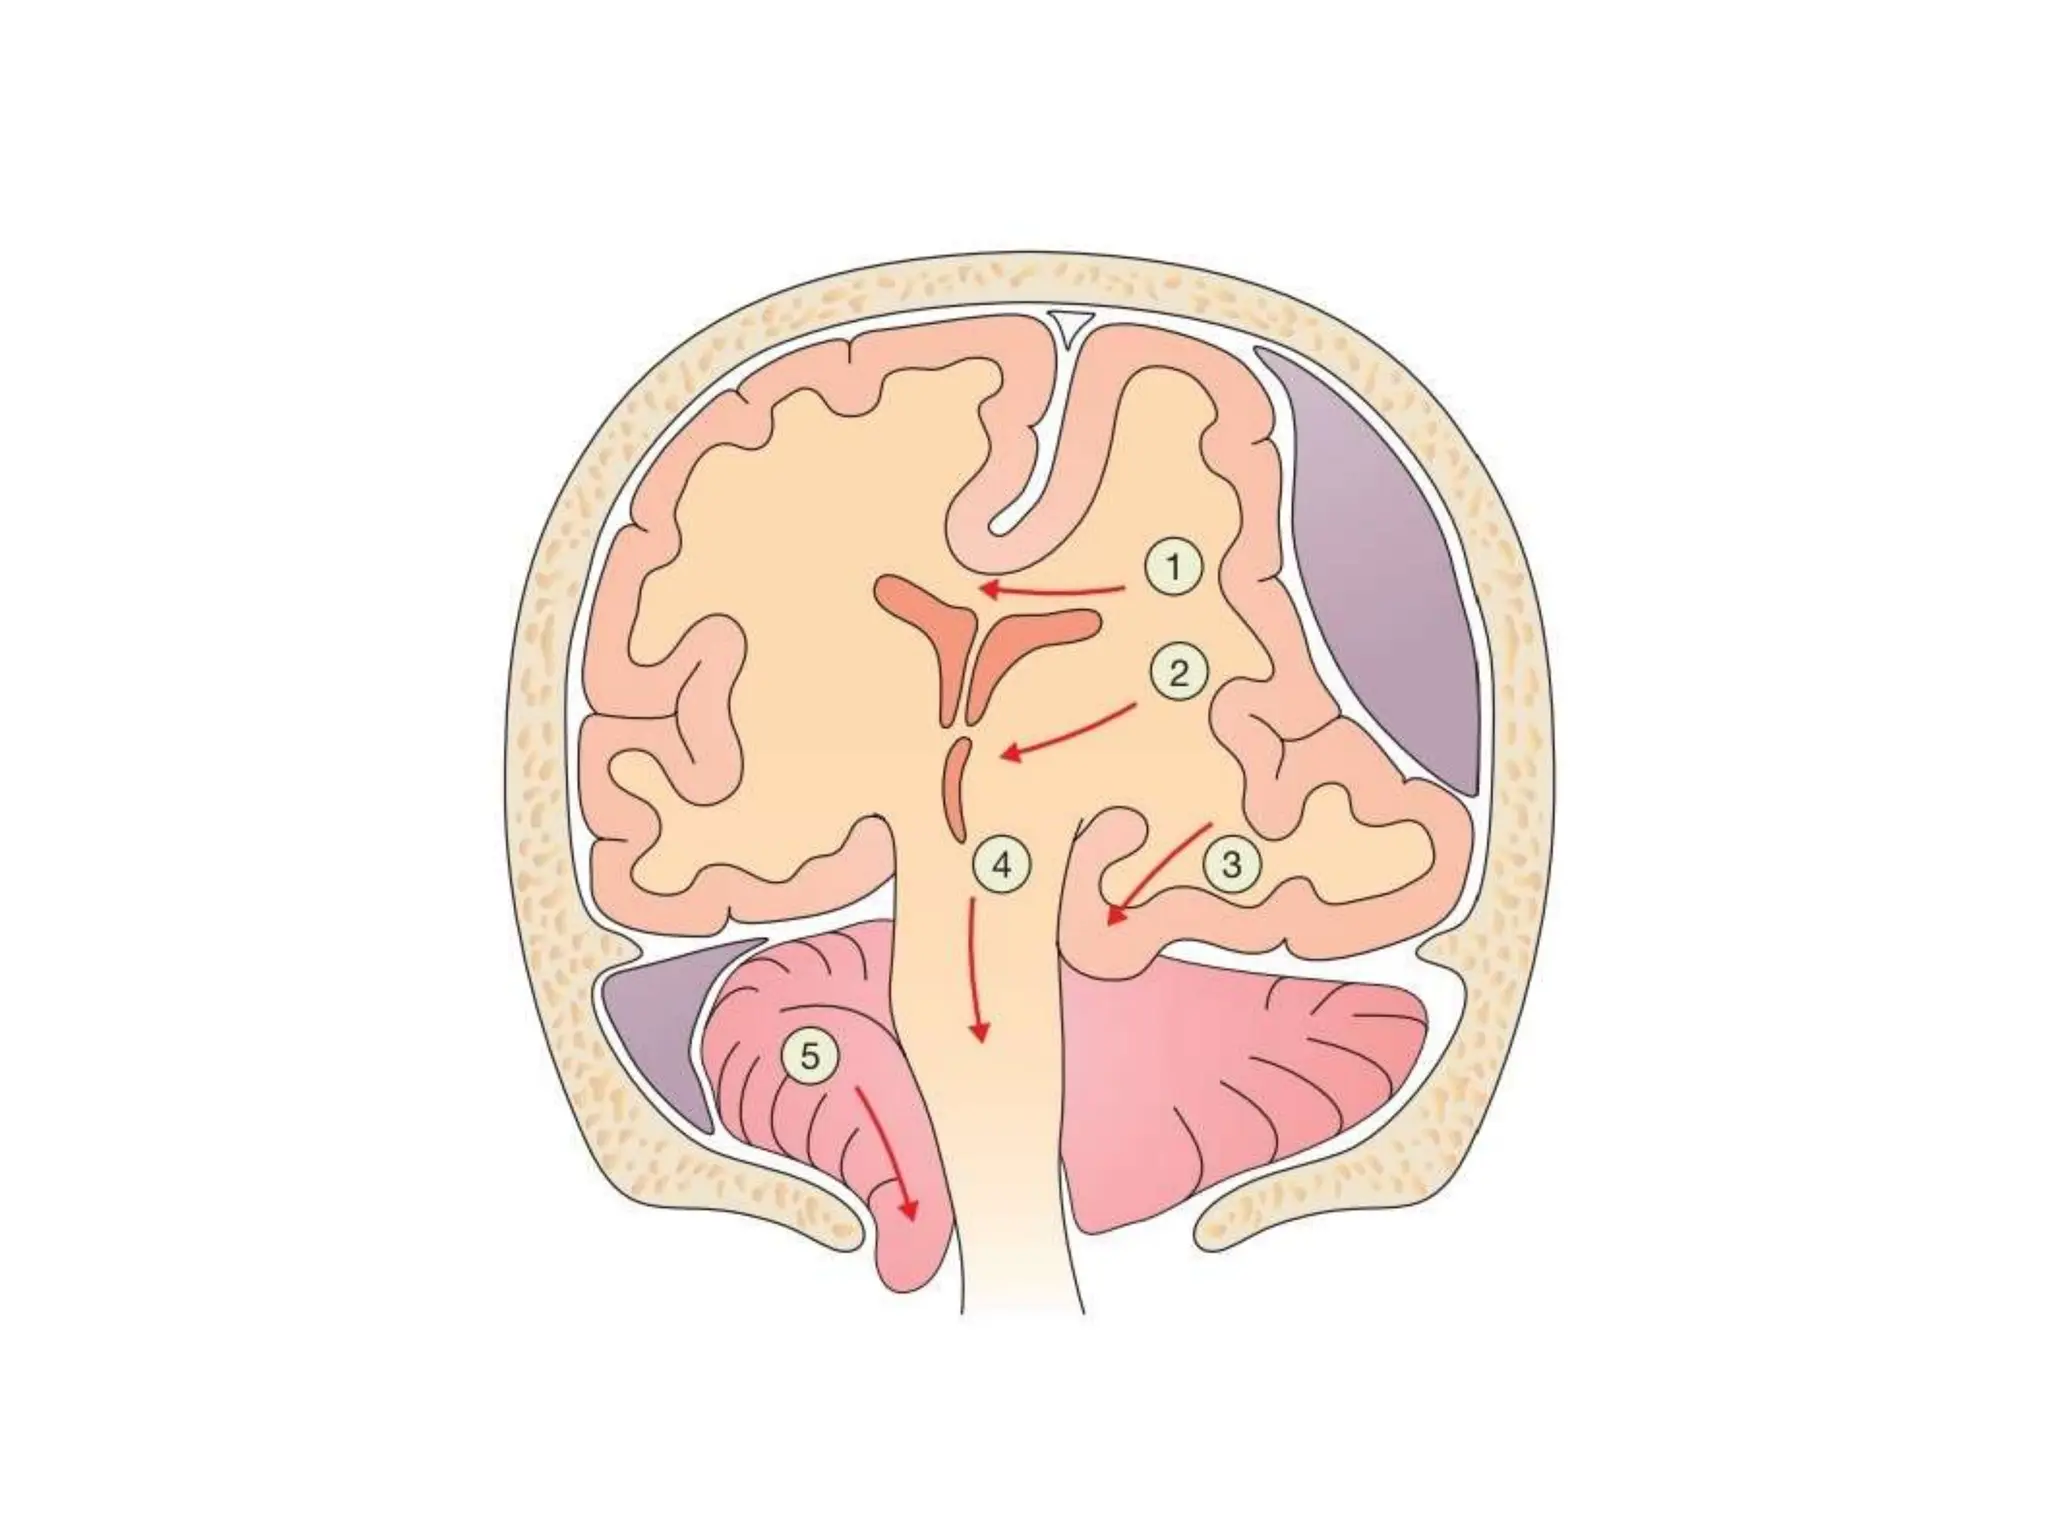

The Monro–Kellie doctrine and

herniation syndromes

The Monro–Kellie doctrineand herniation syndromes • Cerebellar tonsillar herniation through the • foramen magnum compresses medullary vasomotor and respiratory centres, classically producing Cushing’s triad: hypertension, bradycardia and irregular respiration. The • Severe head injury • GCS 3–8 • patient is then said to be ‘coning’, and brainstem death will • result without immediate intervention.